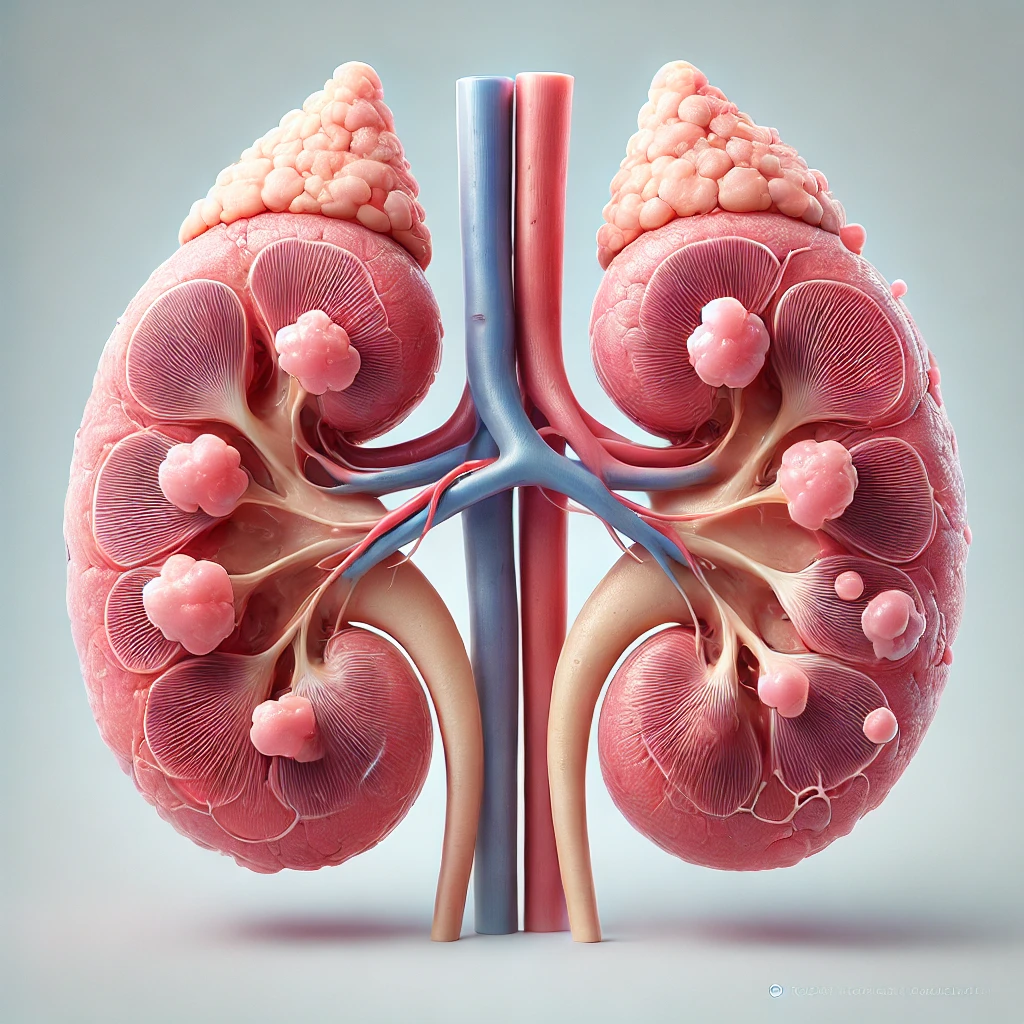

Os rins são órgãos extremamente complexos e desempenham diversas funções vitais no organismo. Muitas pessoas acreditam que a principal função dos rins é apenas “filtrar o sangue”, mas isso é apenas uma parte do que eles fazem. Os rins também regulam o equilíbrio de líquidos, controlam os níveis de eletrólitos como sódio e potássio, participam do controle da pressão arterial e produzem hormônios importantes, como a eritropoetina, responsável pela produção de glóbulos vermelhos.

Além disso, os rins atuam no metabolismo da vitamina D, contribuindo para a saúde óssea, e ajudam a manter o equilíbrio ácido-base do organismo. Ou seja, são órgãos que trabalham 24 horas por dia, de forma contínua e altamente precisa.

Quando ocorre falência renal, todas essas funções são comprometidas, e é justamente aí que entra a diálise como uma forma de suporte — mas não como uma substituição completa.